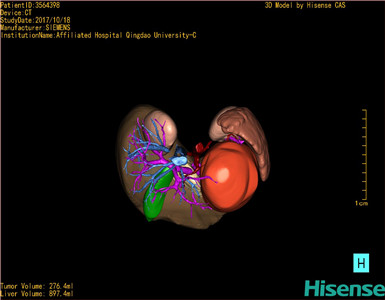

CT结果输入海信CAS系统后行3D重建及手术规划后,于2017-10-19全麻下行“胰体尾肿物切除术+脾切除术+大网膜切除术”手术治疗:

术前三维重建及手术方案设计:

将0.625mm双源薄层CT资料的静脉期和动脉期Dicom格式文件导入海信CAS系统。

通过调节窗宽窗位调整CT序号,对肝实质,胆囊,下腔静脉,肿瘤,肝动脉、门静脉及肝静脉等进行三维重建;系统自动计算肝脏体积。

模拟手术操作,自动计算切除肿瘤体积。肝脏体积为453.7ml,通过比对2-3岁正常肝脏体积为475.97±99.7ml,通过术前模拟手术,精准判断切除后剩余肝脏体积能耐受,避免肝衰竭发生。

术前三维重建:

重建图片